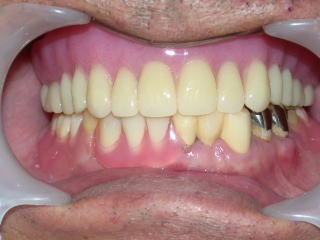

今回、上下義歯とも綺麗に治療したい、とのことでした。

上の義歯は健康保険で作成した総義歯です。

下の義歯はバネのないクラスプレス義歯です。